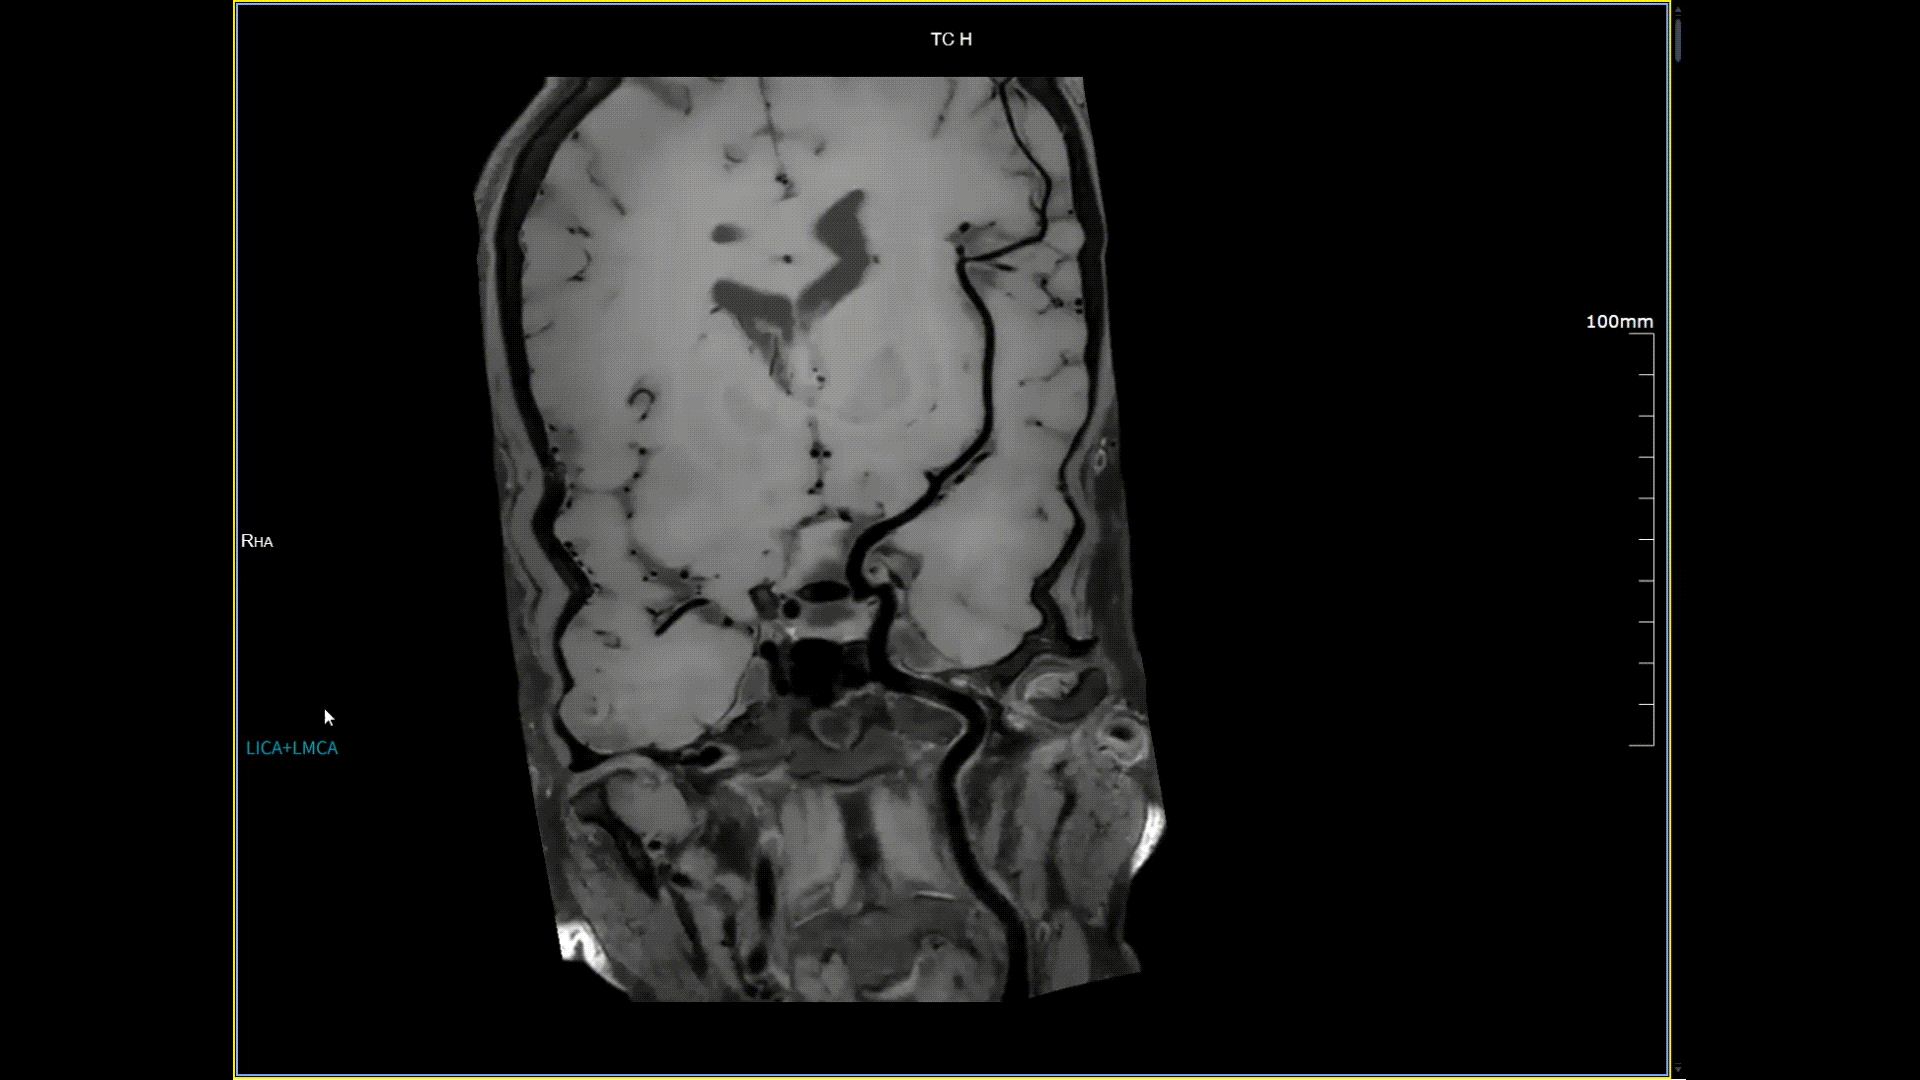

11月3日,一名30岁男性在我院接受了河北省首台5.0T超高场核磁共振头颅血管成像检查,图像清晰精准地反映出患者右侧小脑区域的血管畸形情况,该患者对我院的诊疗实力与服务温度给予充分肯定。相较于传统核磁共振,这台设备实现了“超高场全身各部位成像”的技术突破,它以业界领先的超高性能实现亚毫米级超高清成像,尤其在神经、心血管、体腹、关节等部位肿瘤疾病的早期发现、精准评估、个性化治疗方案制定中提供了的强大影像支持,将为全省乃至周边地区患者带来更优质、更精准的医疗服务。

5.0T磁场强度远高于其他设备,使得氢原子核在磁场中的响应信号极大地增强。这就像在安静的房间里能听清细微的声音一样,高信噪比能让医生看到更微小、更模糊的病变结构。例如上述患者的检查,该设备可以呈现0.2x0.2毫米高分辨率的图像以及动态显示血管走行,使得病变血管的细微解剖结构、分布及其与周边脑组织的关系得以直观呈现,为临床医生进行精准诊断并制定后续治疗方案提供了重要的影像学依据。

头颈血管斑块,分辨率0.4*0.4mm